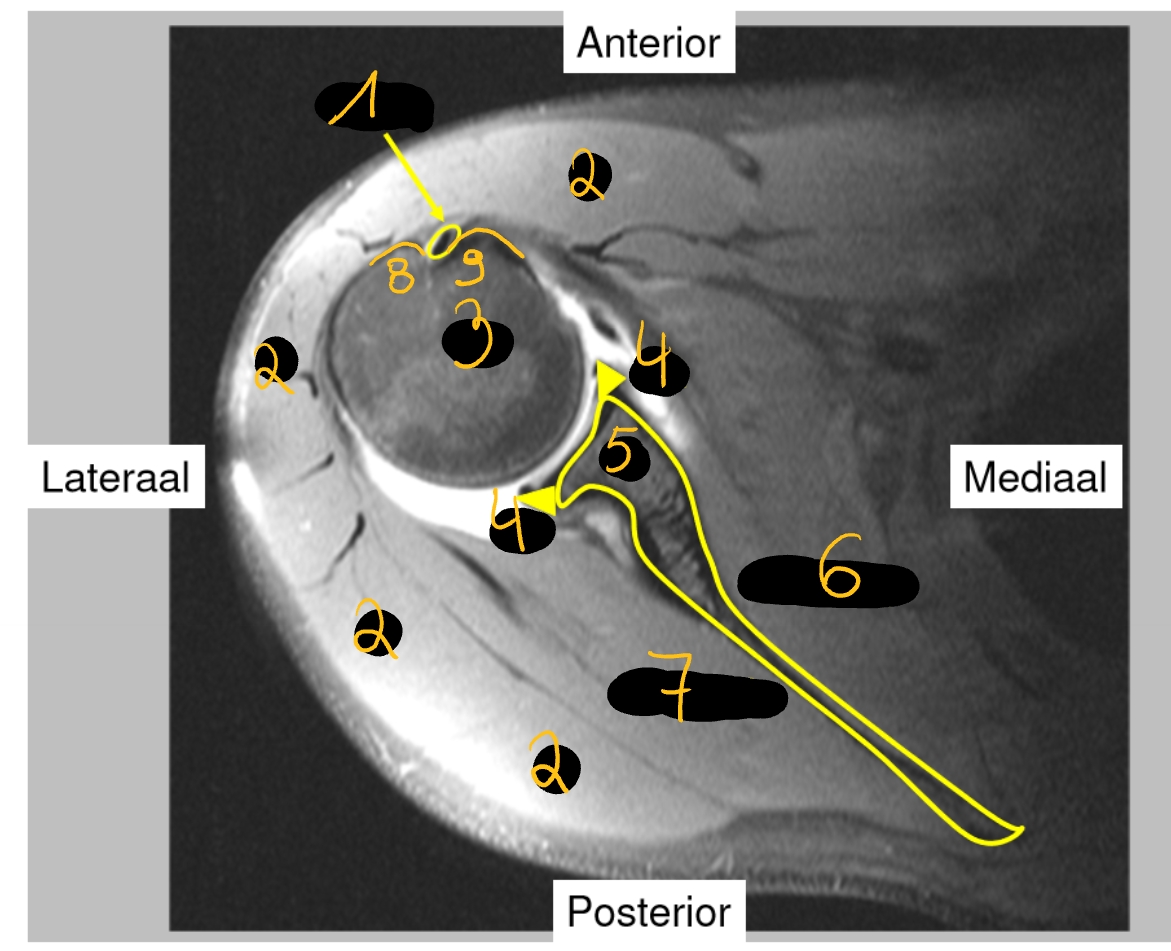

caput longum m. biceps + sulcus intertubercularis

m. deltoideus

caput humeri

labrum glenoidale

scapula

m. subscapularis

m. infraspinatus

tuberculum majus

tuberculum minus

→ rechter schouder (MR): dwarse doorsnede